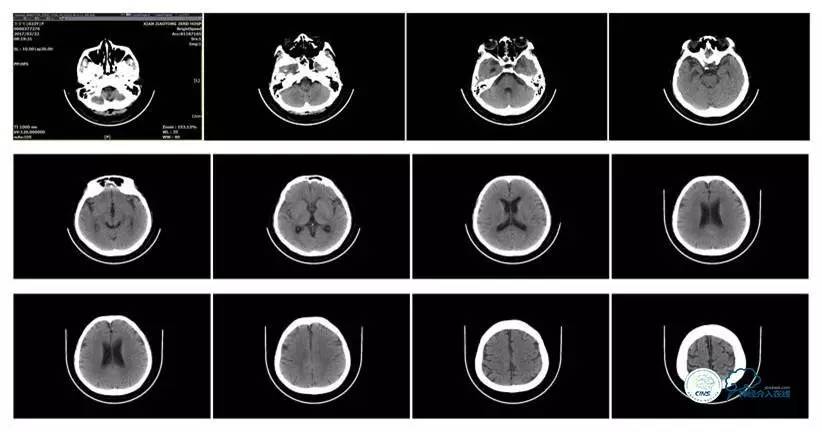

头颅CT

病史:患者于1年余前,因头部外伤在外院行头颅CT提示:未见异常。约3月后患者出现头痛、发作性意识丧失,在当地医院行头颅CT及MRI提示:未见明显异常。诊断为外伤性癫痫,予以对症治疗,未见明显好转。6月余前,无明显诱因出现鼻腔漏液,予以保守治疗,此后鼻腔间断漏液,漏液后头痛缓解。13天前因高热、恶心、呕吐在外院诊断为颅内感染(肺炎链球菌),予以抗炎等对症治疗2周后鼻漏停止,体温正常,CSF常规、生化正常,但头痛仍未缓解,转入我院神经内科治疗。反复腰穿颅内压450-500mmH2O左右,脑脊液常规及生化均正常。颅脑CT及MRI、MRV提示:左侧顶叶硬膜下血肿,鼻窦炎、乳突炎、左侧横窦、乙状窦闭塞、右侧横窦、乙状窦狭窄。予以华法林抗凝治疗2周,维持INR2-3,患者头痛仍无明显缓解,颅内压无下降,转入我科。

诊断:1、右侧横窦、乙状窦狭窄;2、硬膜下血肿(左侧顶);3、继发性癫痫;4、脑脊液鼻漏;5、颅内感染;6、乳突炎;7、鼻窦炎。

病理过程推理:首先是乳突炎—诱发左侧横窦乙状窦血栓最终闭塞,右侧横窦乙状窦狭窄—导致颅内高压,造成头痛及癫痫—持续颅内高压—皮层静脉回流受阻导致自发性硬膜下血肿及自发性脑脊液鼻漏—颅内感染。